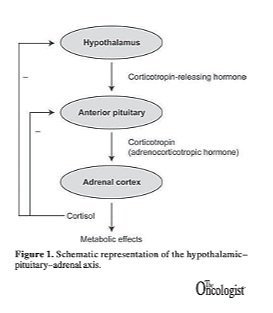

The main driver that enables you to wake bright-eyed and bushy-tailed, and fall into a deep sleep every night is your hypothalamus, which ultimately communicates with your adrenal glands. This communication is actually a three-organ system: your hypothalamus, your pituitary, and your adrenal glands. (Often called the HPA axis)

Proper HPA axis function results in cortisol production from your adrenal glands. The cortisol production fluctuates so that your cortisol is highest when you wake up in the morning and lowest when you go to sleep at night.

In short, American ginseng helps restore the normal fluctuation of cortisol by improving the function of the HPA axis. The reparative process appears to take place within the brain, restoring the negative feedback of cortisol on the hypothalamus and pituitary (see Figure 1). This allows for the proper cortisol fluctuations. This means that the proper ebb and flow of cortisol from the adrenal glands is restored. It also means that when you have a stressful event and have a surge of cortisol, you are able to recover quickly and appropriately.

At all times, your HPA axis is idling in the background, maintaining the proper 24 hour highs and lows of cortisol, along with other hormones. This provides you with sustained energy that gradually fades into fatigue when you should be going to bed.

When there is an acute stress event (think near-miss when driving) your HPA snaps into action and leads to rapid cortisol release so you can get a proper jolt of energy. Ideally, you want to overcome this quickly, and only when your hypothalamus and pituitary are responding properly to high cortisol can you calm down quickly. This makes ginseng both supportive of fatigue and helpful to calm down appropriately.